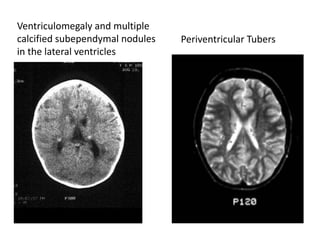

Ventriculomegaly and multiple

calcified subependymal nodules

in the lateral ventricles

Periventricular Tubers

• The CT scan typically shows calcified tubers in the

periventricular area.